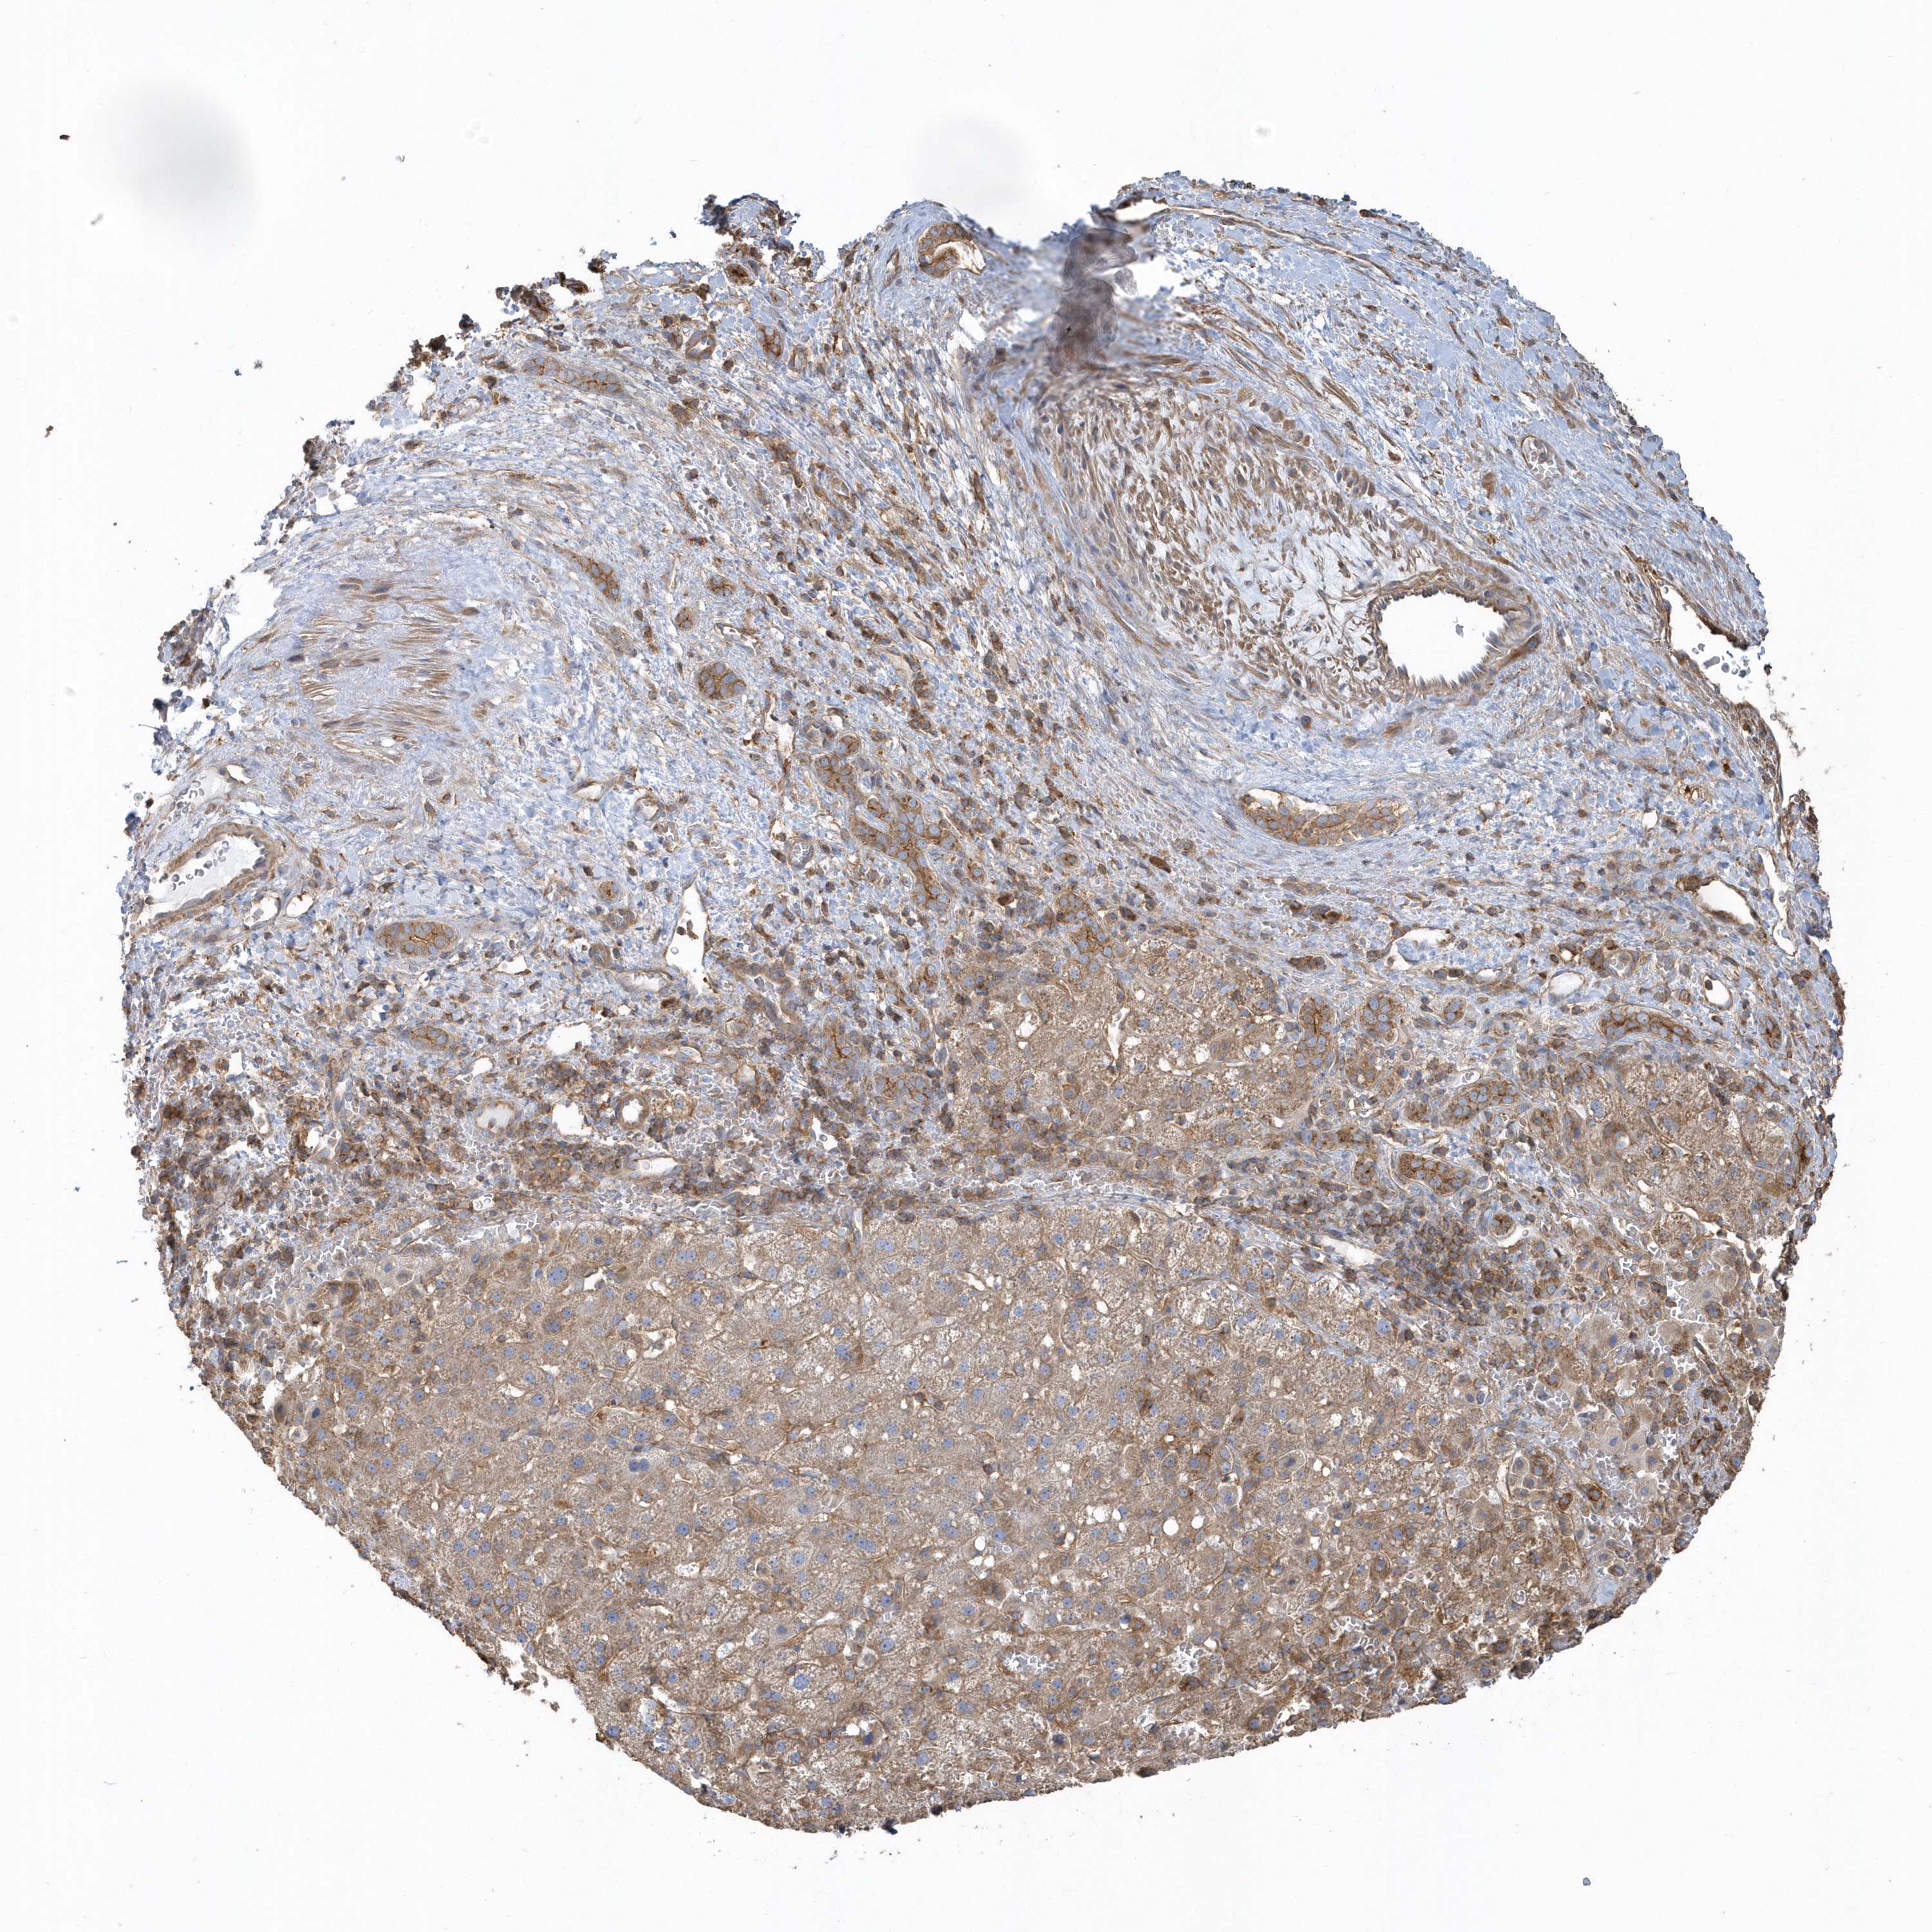

LIVER CANCER - Protein expressioni

A mouse-over function shows sample information and annotation data. Click on an image to view it in a full screen mode. Samples can be filtered based on level of antibody staining by selecting one or several of the following categories: high, medium, low and not detected. The assay and annotation is described here.

Antibody stainingi

Antibody staining in the annotated cell types in the current human tissue is reported as not detected, low, medium, or high, based on conventional immunohistochemistry profiling in selected tissues. This score is based on the combination of the staining intensity and fraction of stained cells.

Each image is clickable and will lead to virtual microscopy that enables deeper exploration of all samples and also displays staining intensity scores, fraction scores and subcellular localization as well as patient and tissue information for each sample.

Antibody HPA036261

Antibody HPA036262

Staining

High

Medium

Low

Not detected

Intensity

Strong

Moderate

Weak

Negative

Quantity

>75%

75%-25%

<25%

None

Location

Nuclear

Cytoplasmic/membranous

Cytoplasmic/membranous,nuclear

Cholangiocarcinoma

Carcinoma, Hepatocellular, NOS